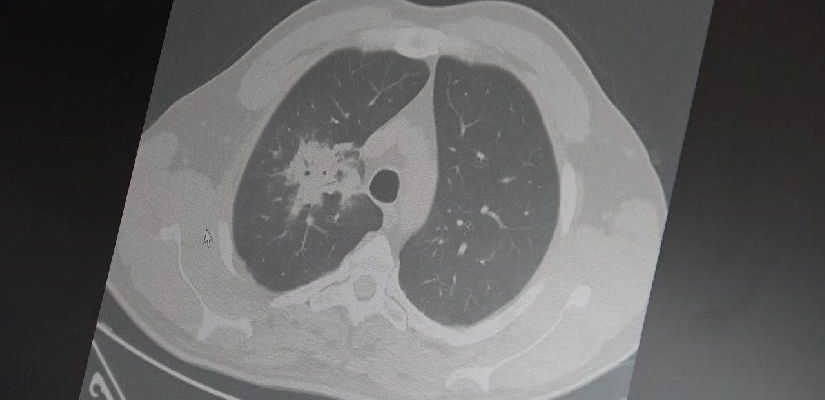

Özkaya, 100’den fazla bilimsel çalışmanın incelendiğini belirterek elektronik sigaraların özellikle akciğer ve ağız bölgelerinde kanser riskini artırabileceğine dair güçlü bulgular bulunduğunu belirtti.

Araştırmalarda insan, hayvan ve laboratuvar verilerinin birlikte değerlendirildiğini aktaran Özkaya, elektronik sigaraların içerdiği kimyasalların hücre düzeyinde zarara yol açtığının ortaya konulduğunu vurguladı.

Elektronik sigaraların DNA hasarı, oksidatif stres ve kronik iltihaplanma gibi kanser gelişiminde kritik rol oynayan üç temel mekanizmayı tetiklediğini belirten Özkaya, “Bu üç faktörün doğrudan kanser oluşumuna neden olduğunu biliyoruz” şeklinde konuştu.

2024 yılında yayımlanan bir çalışmaya da değinen Özkaya, hem geleneksel sigara hem de elektronik sigara kullanan bireylerde akciğer kanseri riskinin, sadece sigara içenlere göre dört kat daha fazla olduğunun bildirildiğini kaydetti.